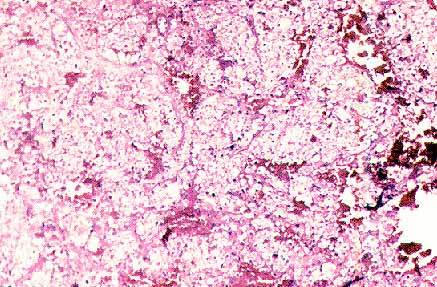

fig. 2

Figura 2.- Comedonecrosis en CCCR putativo. Se trata de un tumor de 16 cm. de diámetro confinado en el riñón. (H&E, 100X)